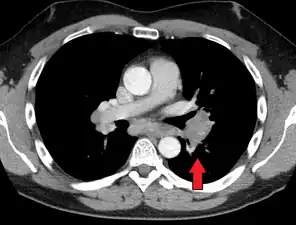

- Hilar adenopathy especially on the person's left (AP CXR)

- Hilar adenopathy especially on the person's left (transverse CT)